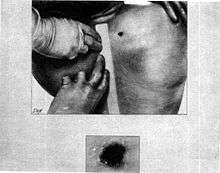

The gunshot wound in the back

- The Bethesda autopsy physicians attempted to probe the bullet hole in the base of Kennedy's neck above the scapula, but were unsuccessful as it passed through neck strap muscle. They did not perform a full dissection or persist in tracking, as throughout the autopsy, they were unaware of the exit wound, at the front of the throat. Emergency room physicians had obscured it when they performed the tracheotomy.

- At Bethesda, the autopsy report of the president, Warren Exhibit CE 387[7] described the back wound as being oval, 6 by 4 millimetres (0.24 in × 0.16 in), and located "above the upper border of the scapula" (shoulder blade) at a location 14 centimetres (5.5 in) from the tip of the right acromion process, and 14 centimetres (5.5 in) below the right mastoid process (the bony prominence behind the ear).

- The concluding page of the Bethesda autopsy report,[7] states: "The other missile [the bullet to the back] entered the right superior posterior thorax above the scapula, and traversed the soft tissues of the supra-scapular and the supra-clavicular portions of the base of the right side of the neck."

- The report also reported contusion (bruise) of the apex (top tip) of the right lung in the region where it rises above the clavicle, and noted that although the apex of the right lung and the parietal pleural membrane over it had been bruised, they were not penetrated, indicating passage of a missile close to them, but above them.

The report noted that the thoracic cavity was not penetrated. - This missile produced contusions of the right apical parietal pleura and of the apical portion of the right upper lobe of the lung. The missile contused the strap muscles of the right side of the neck, damaged the trachea, and made its exit through the anterior surface of the neck.